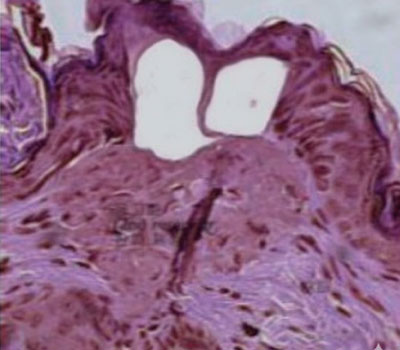

Cómo actúa el láser Tulio 1927 en la piel

Estimulación de colágeno y elastina: El depósito térmico focalizado desencadena respuesta reparativa con neocolagénesis y neoelastogénesis, mejorando firmeza y luminosidad progresivamente en las semanas posteriores.

Microcanales para drug delivery: Las microcolumnas dejan microcanales transitorios que facilitan la penetración de activos tópicos seleccionados, optimizando protocolos combinados en discromías y retexturización.